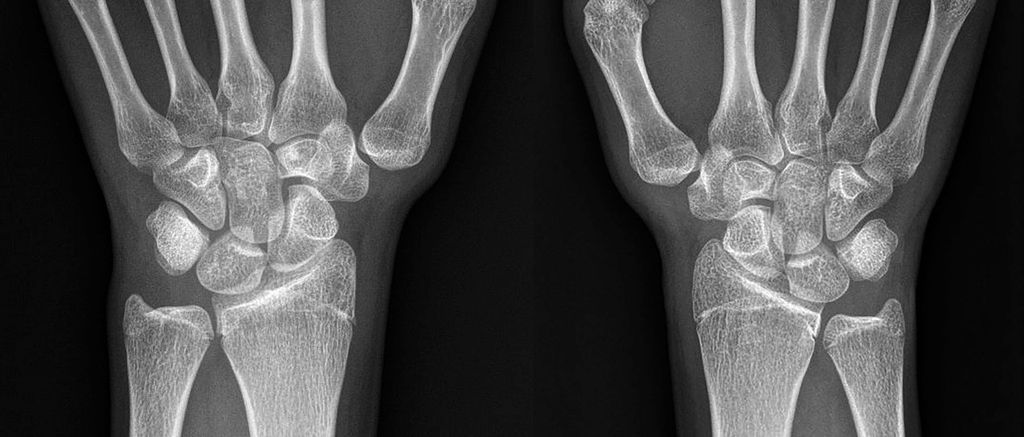

Abb. 3: Röntgenaufnahmen eines erwachsenen Patienten mit manifester Rhizarthrose aufgrund einer beidseitigen Hypoplasie des Trapeziums. Auf der linken Seite ist eine große Ossifikation medial des Trapeziums erkennbar (Eaton-Littler-Grad IV beidseits)13

Chronische Instabilitäten, hervorgerufen durch habituelle Bandlaxizität, führen zu einem vermehrten Stress auf ligamentäre Strukturen an der Basis des ersten Metakarpalknochens und zu Gelenksfehlstellungen. Als Folge kommt es zu einer vermehrten Arthrose der betroffenen Gelenke (siehe Abb. 2 und Abb. 3). Diese Veränderungen gehen mit einer erheblichen Morbidität einher und betreffen vor allem postmenopausale Frauen.12 Nach Eaton und Littler wird die Arthrose des Daumensattelgelenkes in 4 Schweregrade eingeteilt.13 Der Schweregrad und die funktionellen Einschränkungen des CMC1-Gelenkes sind mitunter entscheidend bei der chirurgischen Indikationsstellung und machen den Großteil rekonstruktiver Eingriffe aus.5